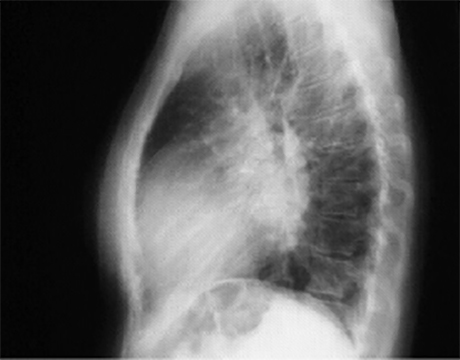

In the lateral view, left atrial enlargement is further reflected by the prominent posterior left atrial shadow. right ventricular enlargement is best seen in this view and is manifested by obliteration of the retrosternal air space.